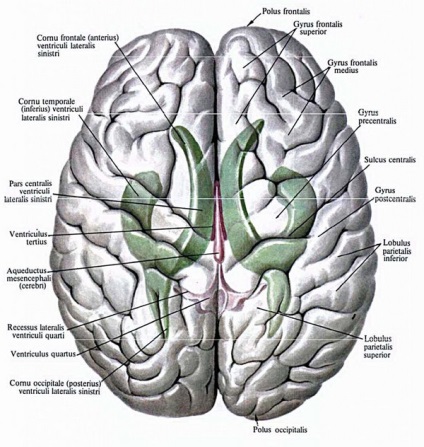

Pentru reprezentarea de ce ventricule mărită a creierului, este necesar să se cunoască aspectul anatomic al problemei. Ventriculi situate în zona creierului într-un grudnichka tânăr, reprezentat printr-un set de formare a cavității, necesare pentru conservarea lichidului cefalorahidian.

structura creierului capacitivi pentru stocarea LCR sunt considerate ventriculilor laterali. Relațiile dimensionale sunt mai mult decât oricare alta. Formarea creierului ventriculului stâng este primul și situat pe marginea din dreapta ─ al doilea.

Al treilea element de ventriculara corelat îndeaproape cu două poziționat lateral prin deschidere dispusă între acoperiș și închiderea stâlpului talamusnogo din față, conectarea unui al treilea element cu ventricular lateral (interventricular). calos (corpul calos) are părți, precum și formarea de ventriculi abdominale sunt situate pe laturile de mai jos doar corpul. Compoziția ventriculilor laterali se prezintă sub formă de față, spate, corn inferior, precum și a corpului.

A patra componentă ventriculară este foarte importantă, este situat în apropiere de cerebel și medulara. Rombovuyu similar cu forma a ceea ce se numește diamant-groapă, care este situat în canalul spinal cu un canal în cazul în care există este a patra componentă sanitare mesaj ventriculare.